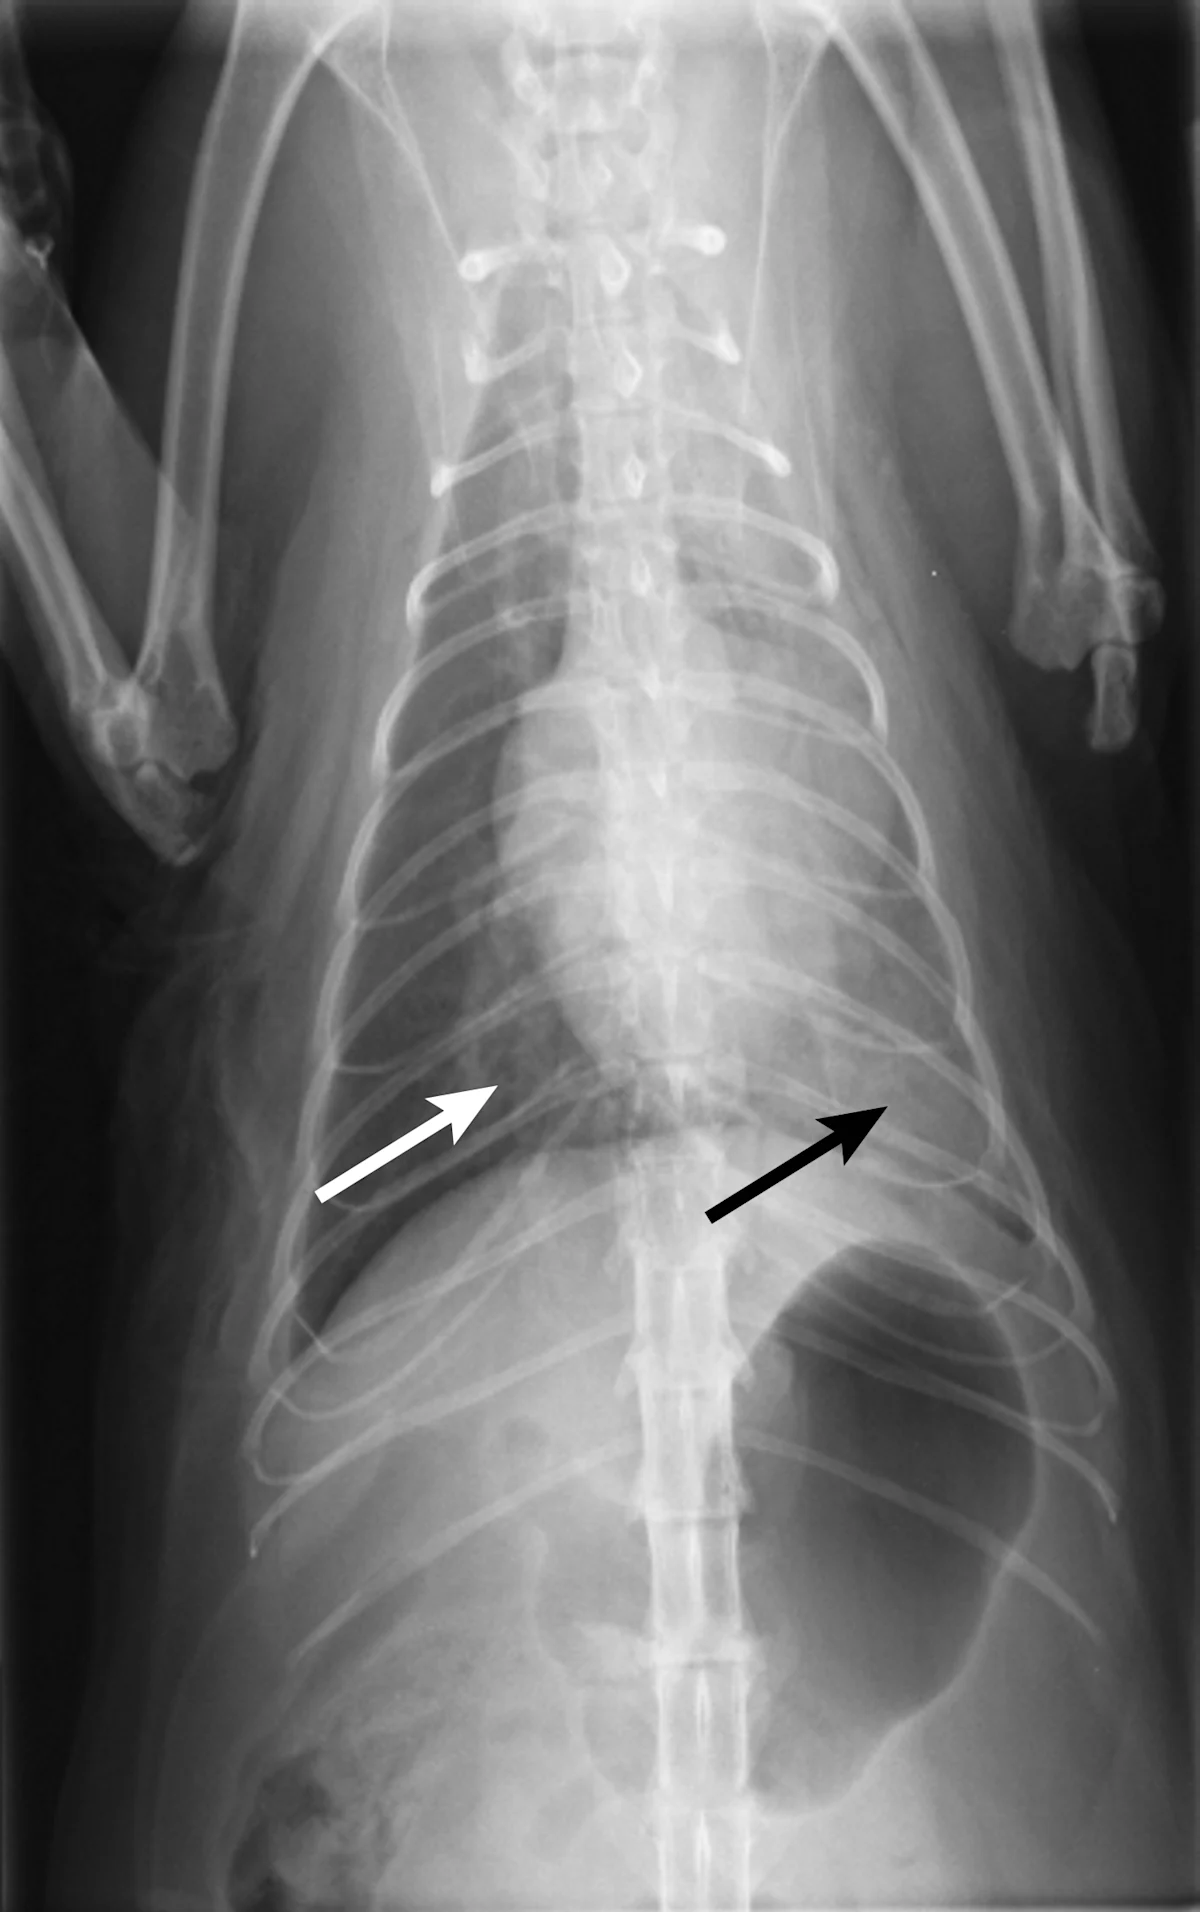

Thoracic radiography (Figure 2) revealed cardiomegaly (vertebral heart score of 8 [range, 7.2–7.8]) characterized by left atrial and ventricular enlargement, distended pulmonary veins, and a pulmonary interstitial pattern. The location of the pulmonary edema was more severe in the left lung lobe. Feline pulmonary edema may not follow the classic caudodorsal and perihilar distribution pattern noted in canine patients.

Figure 2 Right lateral (A) and dorsoventral (B) thoracic radiographs showing cardiomegaly, pulmonary venous distention (white arrows), and pulmonary interstitial densities (black arrows)